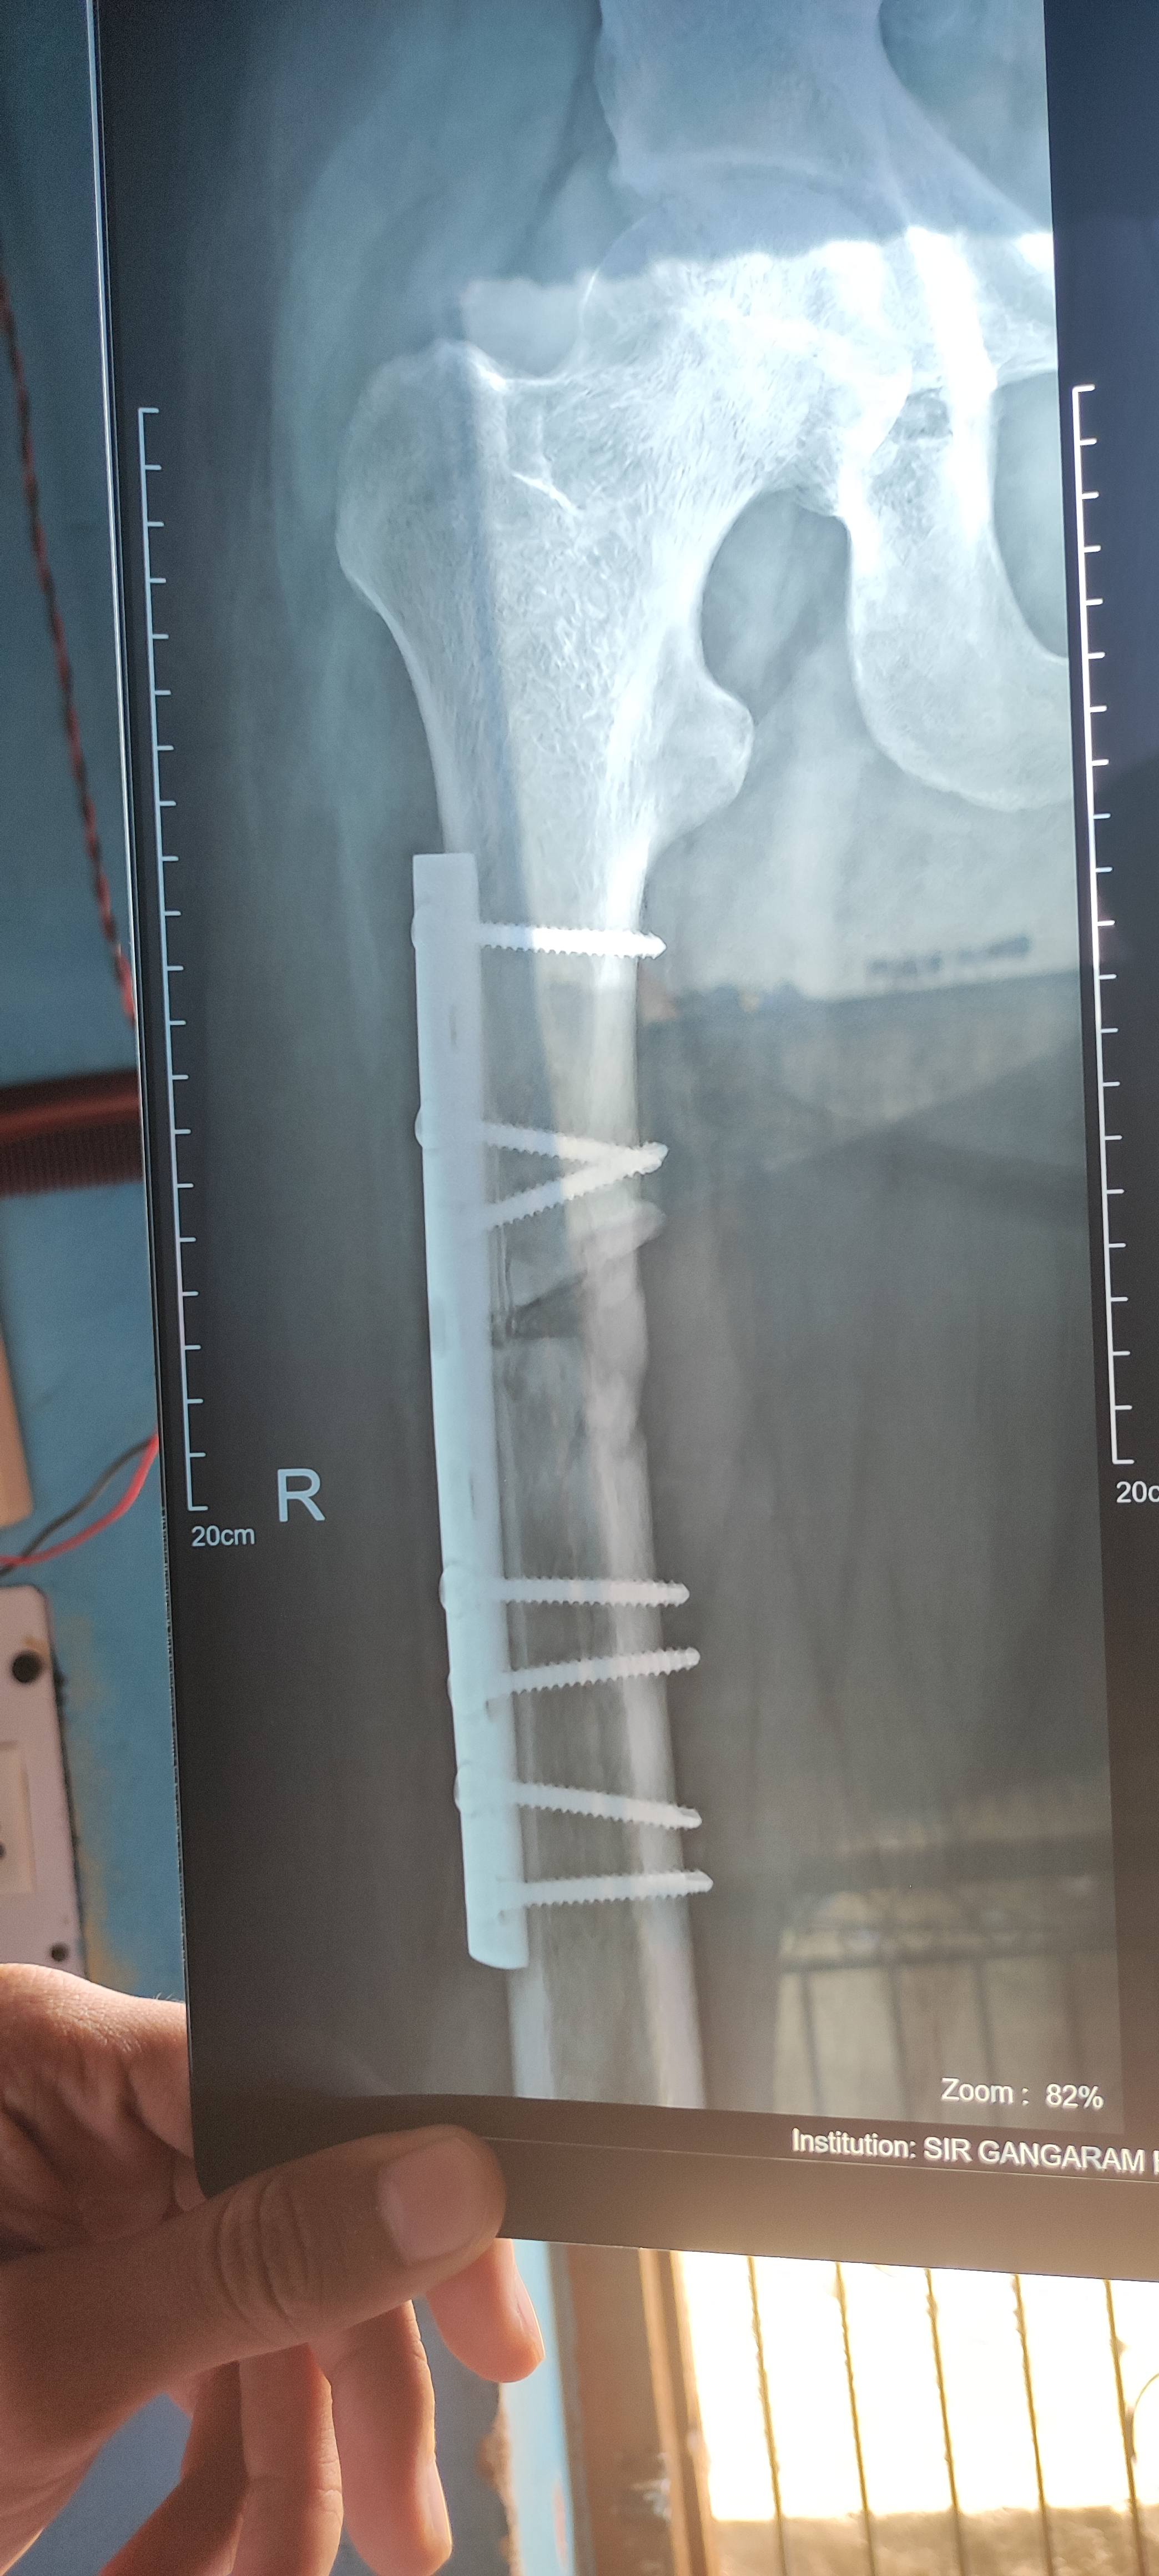

Mam kitna time lg sakta hai

How long time will be take in joint

Please tell me